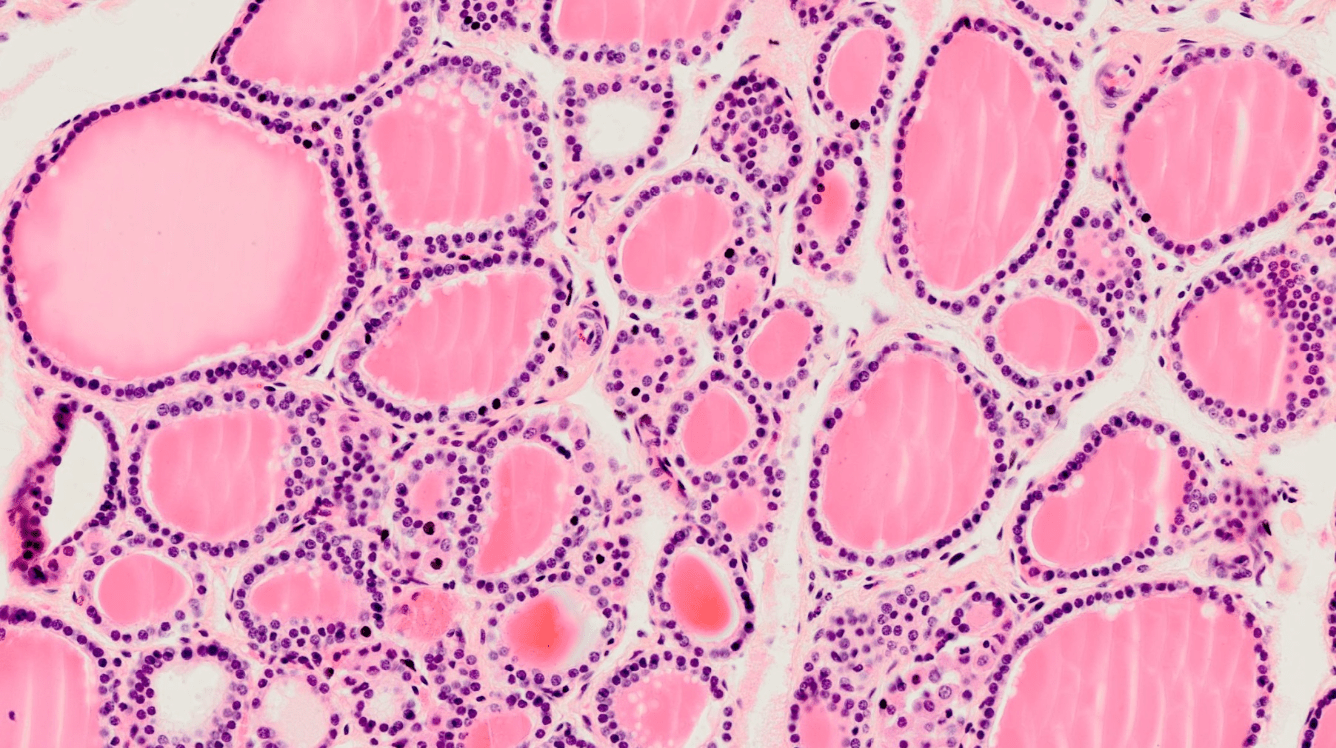

Organdiagnose

Schilddrüse